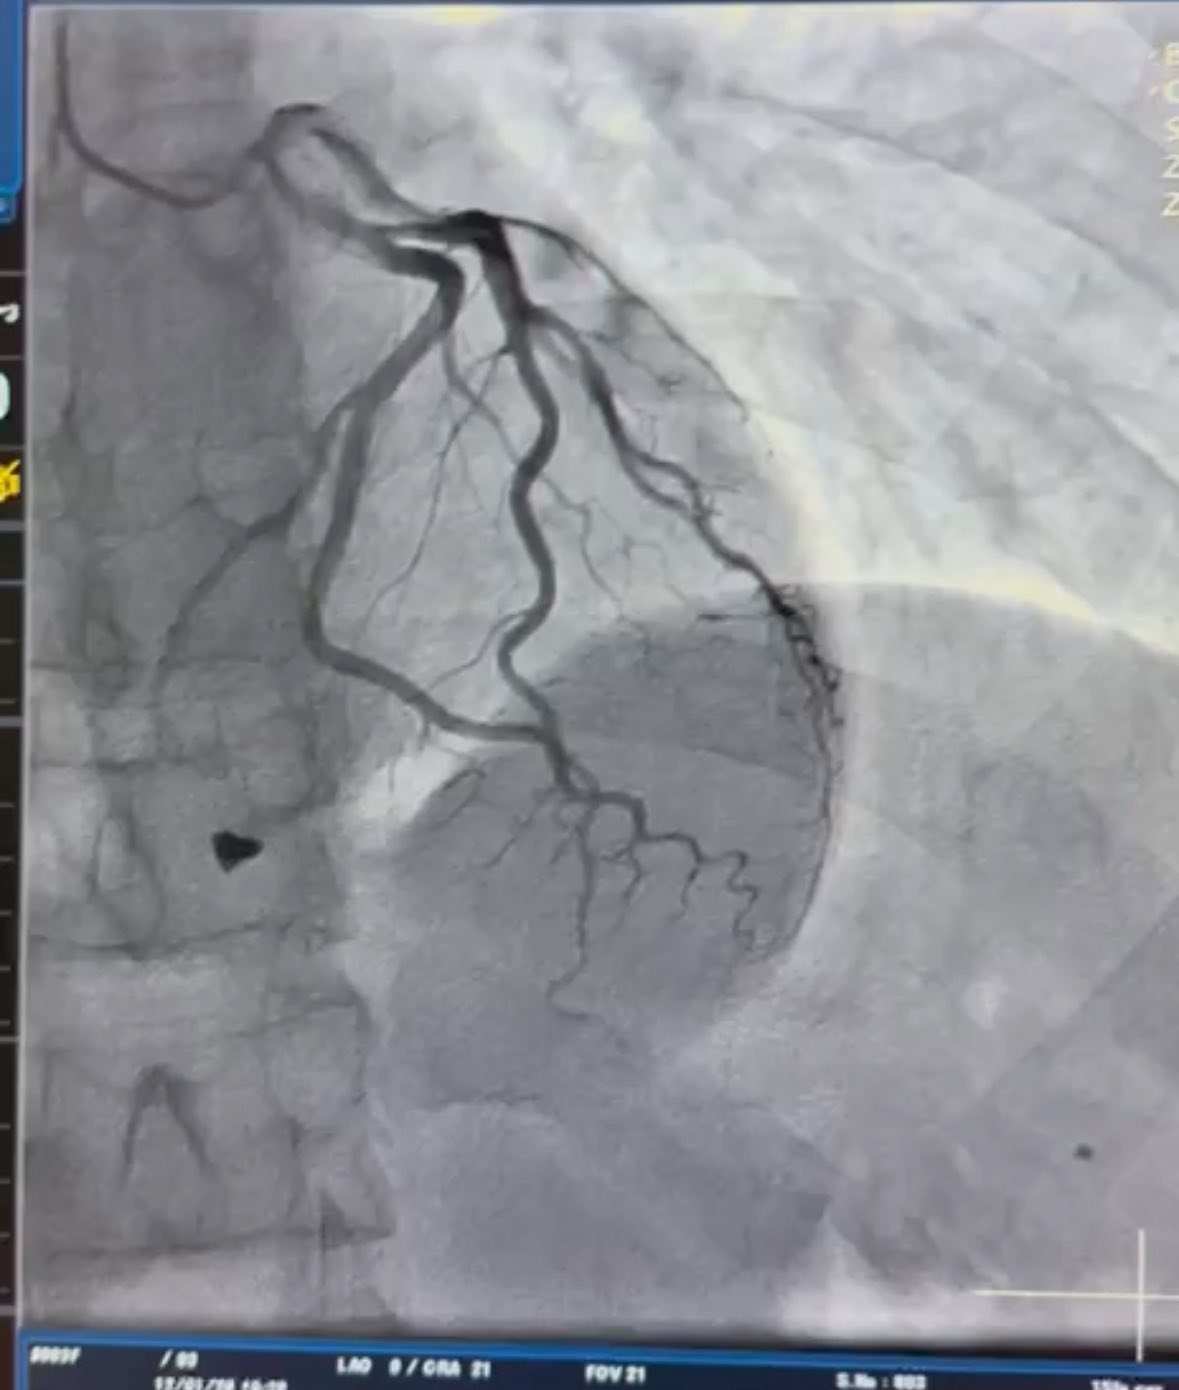

Під час ретельного обстеження медики встановили, що металевий уламок локалізувався в зоні клапанного апарату серця та пошкодив папілярний м’яз тристулкового клапана. Така травма становила пряму загрозу втрати повноцінної роботи клапана і, відповідно, нормального кровообігу.

Після детального аналізу анатомії ушкодження кардіохірургічна команда лікарні ухвалила рішення про негайне оперативне втручання. Фахівці виконали видалення вогнепального осколка та пластику тристулкового клапана, що дозволило відновити його функцію і забезпечити стабільну роботу серця.